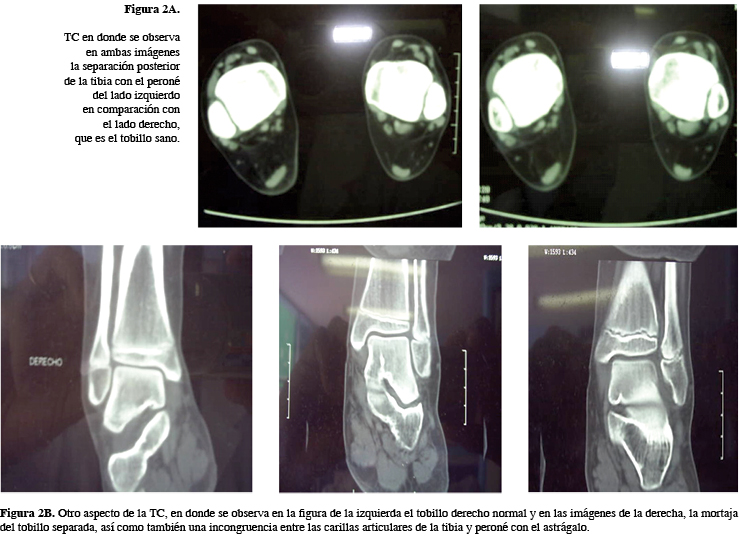

A la exploración clínica, llama la atención el dolor intenso a la palpación sobre la sindesmosis del tobillo. En la Rx simple se observa una apertura de la sindesmosis, por lo que se solicita Rx del tobillo sano para comparar; una vez hecha la comparación y fortaleciendo el diagnóstico de diástasis de la mortaja del tobillo (Figura 1), se solicitaron TC, en donde se pudo corroborar la lesión (Figura 2)